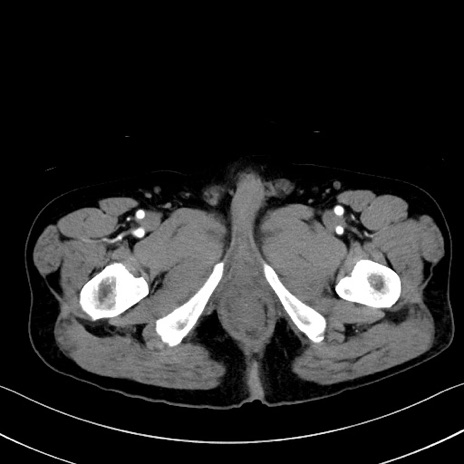

冠状断像